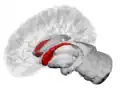

The caudate nuclei are located near the center of the brain, sitting astride the thalamus. There is a caudate nucleus within each hemisphere of the brain. Individually, they resemble a C-shape structure with a wider "head" (caput in Latin) at the front, tapering to a "body" (corpus) and a "tail" (cauda). Sometimes a part of the caudate nucleus is referred to as the "knee" (genu).[7] The caudate head receives its blood supply from the lenticulostriate artery while the tail of the caudate receives its blood supply from the anterior choroidal artery.[8]

The head and body of the caudate nucleus form part of the floor of the anterior horn of the lateral ventricle. After the body travels briefly towards the back of the head, the tail curves back toward the anterior, forming the roof of the inferior horn of the lateral ventricle. This means that a coronal (on a plane parallel to the face) section that cuts through the tail will also cross the body and head of the caudate nucleus.